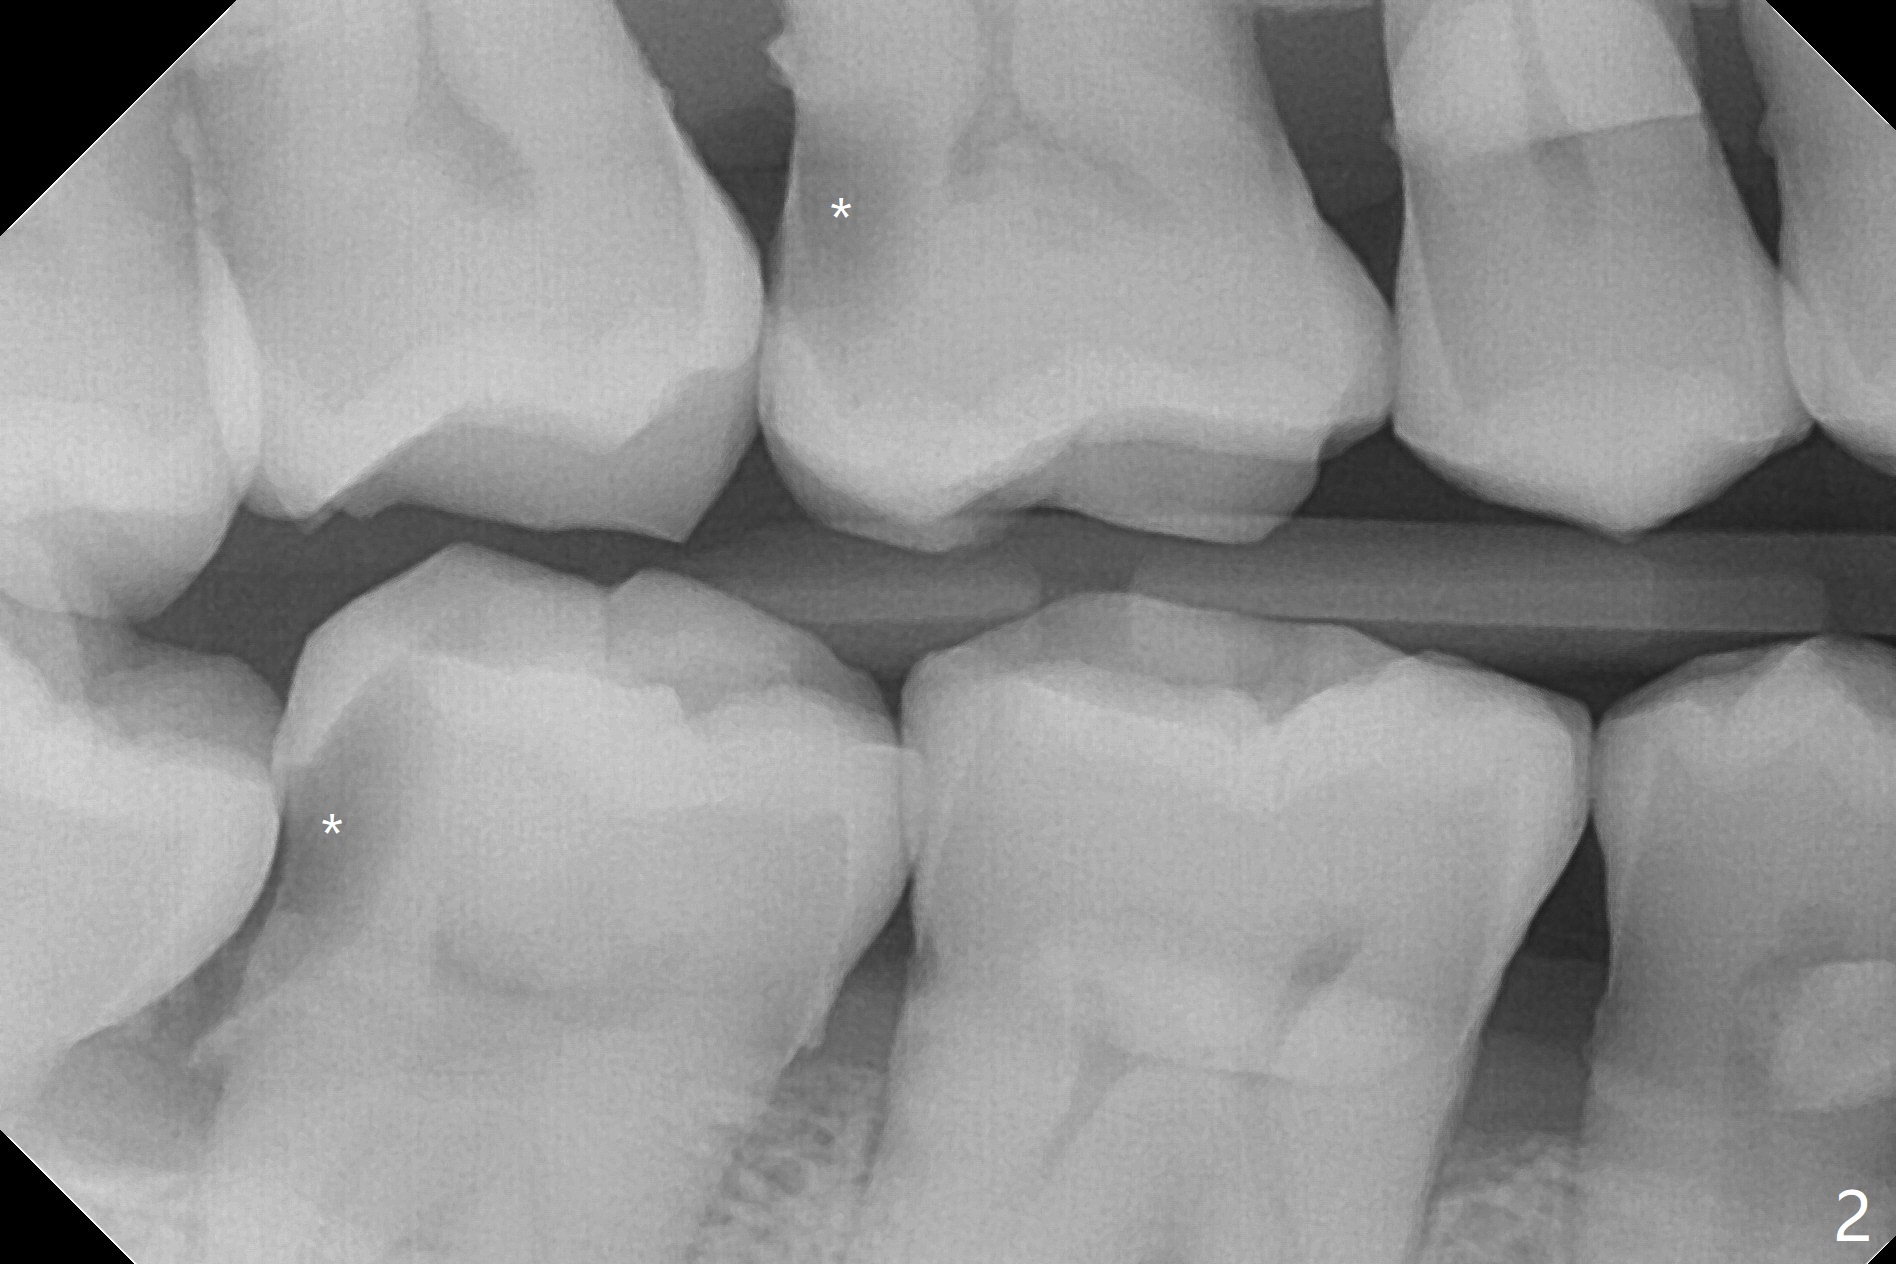

51岁男牙周炎,坚持他有蛀牙,全景片和根尖片显示右上第一右下第二磨牙远中龋(图一,二 *)。稍微分离右下智齿颊侧牙龈,分冠拔除,纱布塞入拔牙窝,好像第二磨牙远中龋去除比较容易,所以决定同期树脂修复。为了防止树脂脱落,去除龋坏后,在咬合面制备鸠尾。当时为了图省事,没有使用成型片,反而费时,尽管用纱布止血隔离,效果不好,徒手堆树脂不方便,尤其是牙龈处。下次必须用二号成型片,剪去近中牙龈部分,让远中部分完全入位,特别是牙龈缘。最后在拔牙窝放置胶原塞,缝合,防止干槽症。七天后缝线消失,伤口仿佛愈合,右下七没有症状。右上第一磨牙DO树脂修复,好像接近远中舌侧牙髓角,术后全景片(图三)似乎证实这一点。